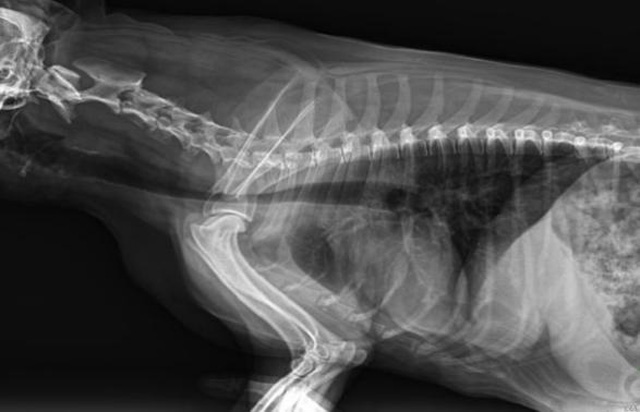

寵物DR是動物專用的數字化攝影系統,x線的穿透能力、低的輻射劑量,輻射劑量比X光低:熒光作用和感光作用,可以穿透動物身體的結構顯示成像,動物的各個部位成像輔助獸醫診療。寵物DR采集時間10ms以下,成像時間僅為3秒,從檢查到出診斷報告大約5—10分鐘。較高的空間分辨力和低噪聲率,可獲得高清晰圖像。 DR成像數字化處理的特點可進行后處理。提高了病灶的檢出率,這樣大大提高檢查的準確率提高診斷準確率避免漏診誤診等情況。